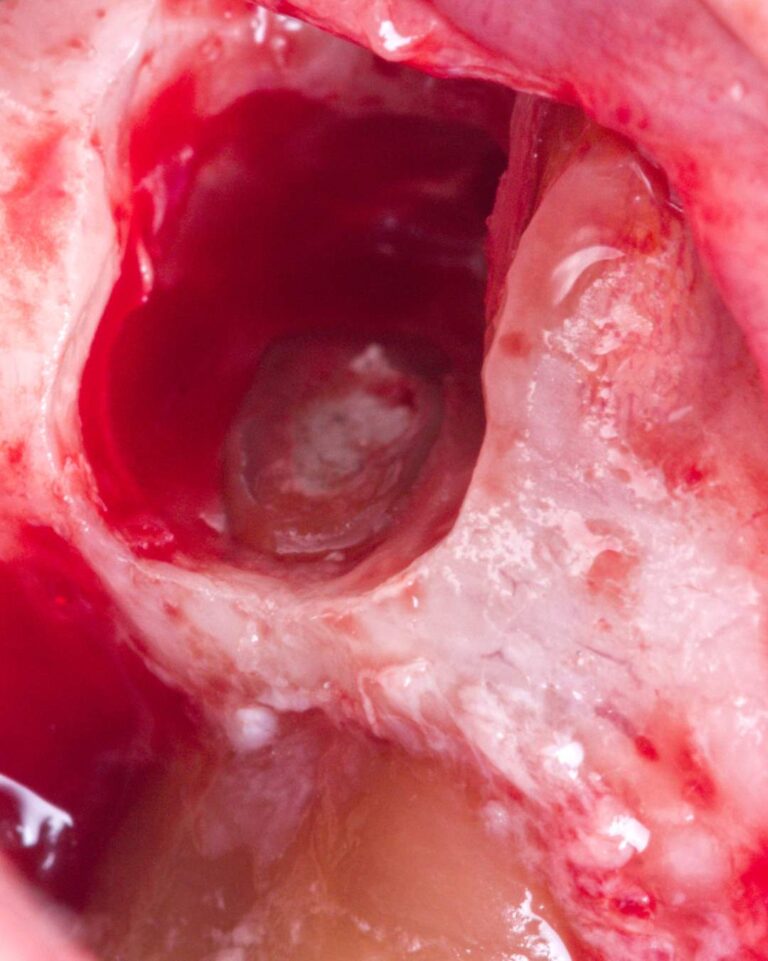

Cirurgia apical para remoção de quisto